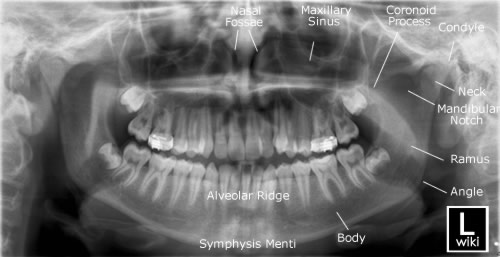

It is performed using a technique called "tomography". The X-ray tube moves around the head, the x-ray film moves in the opposite direction behind your head. This generates an image slice where the mandible and teeth are in focus, and the other structures are blurred.

* Mandible fractures are often bilateral.* Panoramic view of mandible to view the fracture.

* Determine site and direction of fracture lines.

* Relationship of teeth to fracture lines.